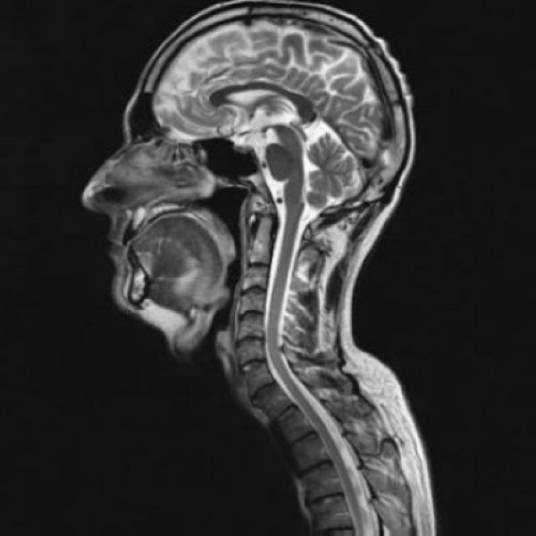

核磁共振技术

的有关信息介绍如下:

核磁共振技术可以直接研究溶液和活细胞中相对分子质量较小(20,000 道尔顿以下)的蛋白质、核酸以及其它分子的结构, 而不损伤细胞。

与此同时,其可以解决蛋白质、DNA/RNA、碳水化合物的结构,可以鉴定动态特征。